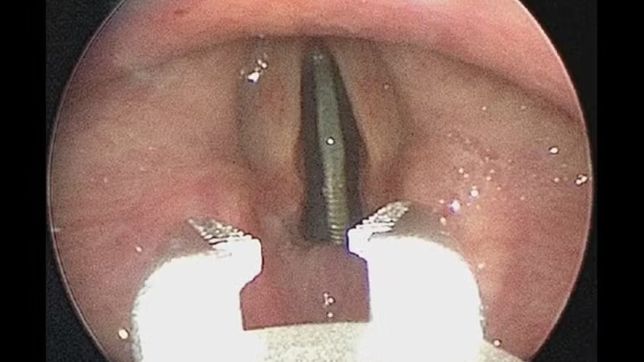

Na esperança de chegar à raiz do problema, eles radiografaram seu tórax, que mostrou que a moeda estava "situada verticalmente dentro da subglote" (a área entre as cordas vocais e a traqueia), que permitia a passagem do ar, apesar de causar desconforto.

Sob anestesia geral, o adolescente foi submetido a broncoscopia, uma operação que envolve sondar as vias aéreas com uma pinça flexível. A moeda foi retirada sem provocar danos ao paciente. Ele recebeu alta e teve de volta a sua moeda.